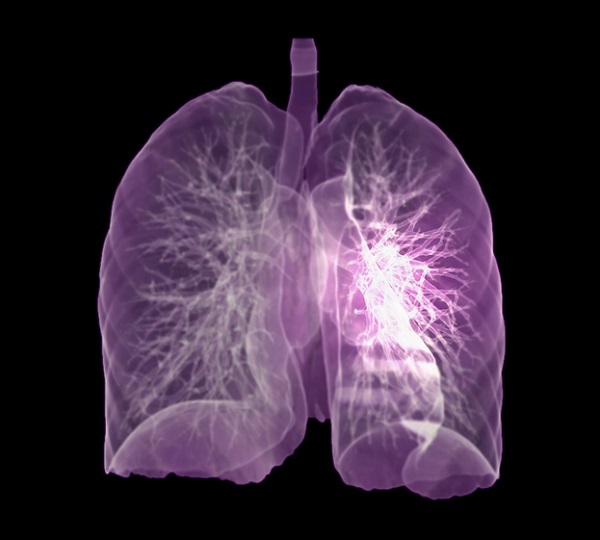

호흡 곤란

호흡 곤란은 폐암의 증상입니다. 폐암 환자의 약 4분의 1이 호흡곤란 증상을 보이며, 이는 다발성 폐 전이가 양측 증상을 나타내거나 악성 흉막삼출이 폐암과 함께 발생할 때 발생합니다. 폐암은 점차 흉통을 악화시킬 수 있으며, 폐암이 진행됨에 따라 폐암의 크기가 커지거나 그 부위에 물이 차게 되면 호흡이 흉막을 자극하여 호흡곤란과 흉통을 유발할 수 있습니다. 격렬한 작업이나 격렬한 운동을 하지 않았더라도 호흡곤란이 발생하거나 호흡이 불편한 경우 의사의 진찰을 받는 것이 좋습니다.

쉰 목소리

폐암으로 인한 악성종양이 성대의 폭을 조절하는 신경을 손상시키면 목소리는 자연스럽게 증상을 멈춘다. 폐암이 폐와 기관 사이에 있는 신경을 건드리면 소리를 내는 성대를 조절하는 신경이 폐의 일부를 통과하여 성대가 마비되어 소리가 멈춥니다. 또한 폐암은 잦은 기침을 동반하기 때문에 성대에 무리를 줄 수 있습니다. 폐암에 걸려 목이 쉰다면 폐암 3기 이상일 가능성이 큽니다. 이러한 증상을 포함하는 증상이 있는데도 쉰 목소리가 이유 없이 호전되지 않는다면 폐암을 의심해볼 수 있습니다.